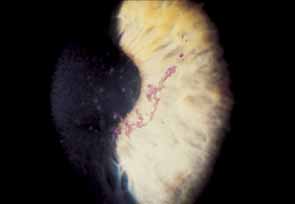

Fig. 17 Sectoral iris atrophy, status post–herpes zoster ophthalmicus. Note

the moth-eaten appearance of iris in sectoral area, underlying

a corresponding area of sclerokeratitis and limbal vascularization. Fig. 17 Sectoral iris atrophy, status post–herpes zoster ophthalmicus. Note

the moth-eaten appearance of iris in sectoral area, underlying

a corresponding area of sclerokeratitis and limbal vascularization.

|